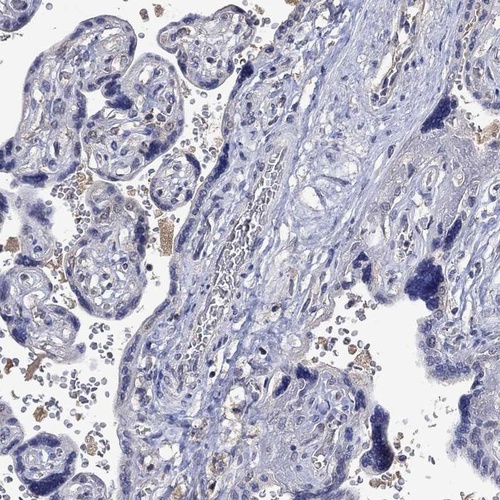

Immunohistochemistry analysis in human testis and placenta tissues using Anti-PTPN20 antibody. Corresponding PTPN20 RNA-seq data are presented for the same tissues.